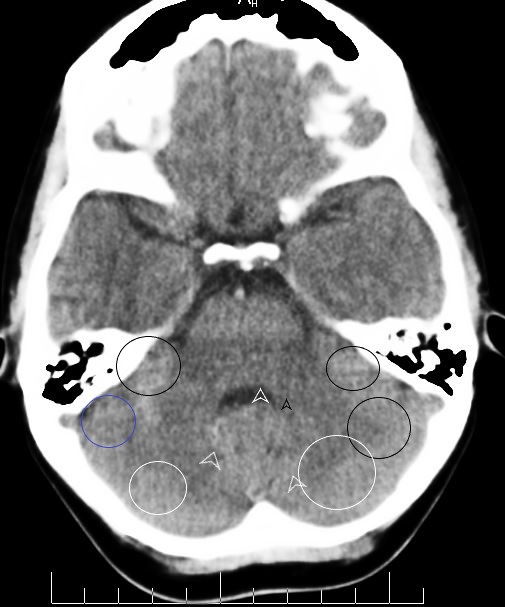

CCT-Auswertung (Hamersche Herde) - Grundgebühr - 30 €